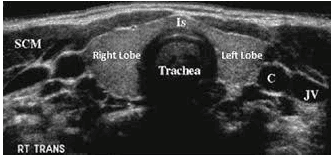

Siêu âm bệnh lý tuyến giáp là sử dụng sóng âm thanh để tạo ra hình ảnh của tuyến giáp nằm trong vùng cổ. Đây là một phương tiện thường được sử dụng để khảo sát tuyến giáp to, các khối u hoặc nốt sần được tìm thấy tại vùng này hay khi bệnh nhân có hội chứng cường giáp, suy giáp.

Siêu âm có bản chất là một phương tiện hình ảnh học an toàn và không gây đau đớn, tạo ra hình ảnh bên trong cơ thể bằng sóng âm thanh. Tương tự như vậy, siêu âm bệnh lý tuyến giáp là tạo ra hình ảnh của tuyến giáp và các cấu trúc lân cận ở vùng cổ.

Tuyến giáp nằm ở phía trước cổ, có hình dạng như một con bướm, với hai thùy ở hai bên cổ và được nối lại với nhau bởi một dải mô hẹp. Đây là một tuyến nội tiết sản xuất và giải phóng hormone giáp vào trong máu, giúp điều chỉnh các chức năng chuyển hóa của cơ thể. Cơ quan này cũng thường được phát hiện thấy tăng kích thước, có các u cục hoặc nốt sần bất thường. Chính vì vậy, vai trò của siêu âm lúc này là rất nhạy cảm để chẩn đoán bệnh lý tuyến giáp.

Hình ảnh kết quả siêu âm tuyến giáp